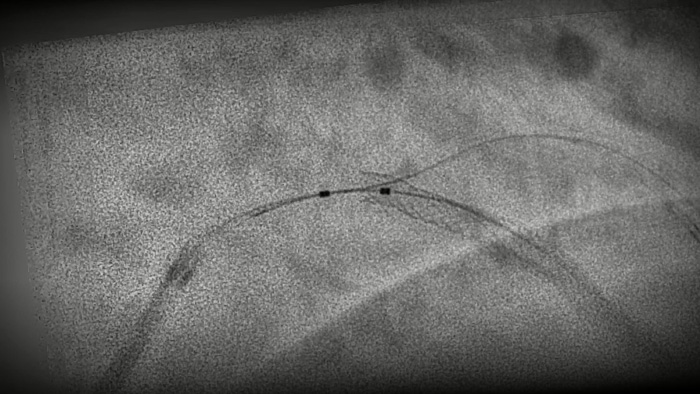

Una tecnología exclusiva de Philips, crea una vista en tiempo real de las arterias coronarias compensada por el movimiento. Un angiograma coronario resaltado se superpone sobre una imagen fluoroscópica 2D en vivo, y crea una hoja de ruta coloreada que se ajusta automáticamente, proporciona retroalimentación visual continua sobre el posicionamiento de guías y catéteres.

StentBoost Live10 le ayuda rápidamente a verificar el posicionamiento antes y después de desplegar balones, stents y dispositivos intracoronarios para ver la implementación y confirmar la expansión completa. Y todo ello se realiza en tiempo real, por lo que ya no tendrá que esperar a recibir nuevas imágenes antes de reposicionar.